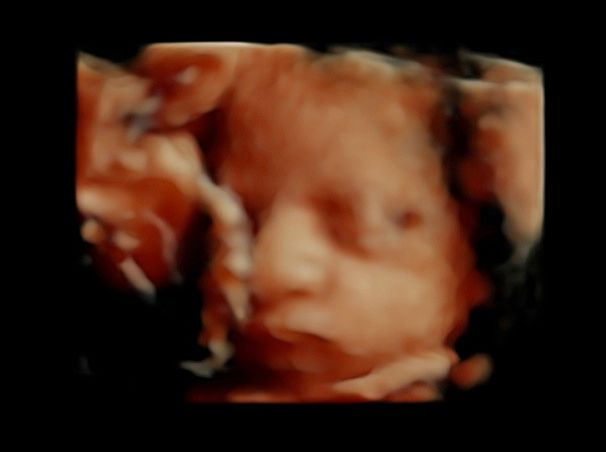

Subito dopo la laurea, il dottor Tommaso Incandela, ha conseguito l'idoneità ospedaliera nella branca di Ostetricia e Ginecologia con il giudizio finale di ottimo. Dall'Aprile 1977 fino al Gennaio 1982, su delibera del consiglio di facoltà, ha svolto la funzione di medico interno della seconda cattedra di Ostetricia e Ginecologia con mansioni didattiche, di assistenza e di cura. Dal Luglio 1981 al mese di Ottobre 1992 ha ricoperto la funzione di assistente di ruolo presso la seconda divisione di Ostetricia e Ginecologia dell'Ospedale Civico e Benfratelli di Palermo. Dal 1 Novembre 1992 fino alla fine di Giugno 1998 è stato dirigente medico del Consultorio familiare di Santa Flavia. Dal Luglio 1998 a tutt'oggi si dedica a tempo pieno all'attività libero professionale occupandosi di ecografia ostetrica e ginecologica con particolare riguardo per la diagnosi prenatale di patologie cromosomiche e malfomative (studio di aneuploidie cromosomiche su DNA fetale prelevato dal sangue materno, amniocentesi precoce, ecocardiografia fetale, ecografia morfologica e cardiotocografia) tutte queste indagini sono inserite nel monitoraggio della gravidanza. Il dottor Tommaso Incandela si occupa altresì di diagnosi precoce e terapia di patologie del tratto genitale inferiore e nel corso degli anni ha acquisito una notevolissima esperienza nell'ambito della terapia conservativa dei fibromi uterini mediante terapia farmacologica e/o inserimento di spirali medicate al progestinico. Da un punto di vista chirurgico il dottor Incandela si occupa di patologie del corpo uterino ivi compresa l'asportazione di fibromi con conservazione dell'utero stesso anche in pazienti meno giovani e con assenza di desiderio di prole. Il dottor Incandela si occupa anche di chirurgia del pavimento pelvico con particolare riguardo per la terapia dell'incontinenza urinaria, dei prolassi uterini e vescicali e delle lacerazioni antiche da parti pregressi.

Foto e video